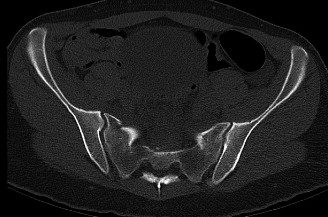

Expected surgical outcomes following revision surgery for recurrent disc herniation? CASE 3 A 27-year-old previously healthy woman is transferred directly to your trauma center with severe low back pain after jumping from an overpass in an apparent suicide attempt. The trauma team completes the primary survey, and the patient is hemodynamically stabilized with fluid resuscitation. On secondary survey she is found to have significant pain with examination/manipulation of her pelvis. Lower extremity examination demonstrates multiple superficial abrasions and grade 4/5 strength with great toe extension and ankle dorsiflexion on the left. Inspection of the perineum shows no blood at the urethral meatus or rectum; however, rectal tone and perianal sensation are decreased. The remainder of the examination is unremarkable. An anteroposterior view of the pelvis demonstrates unilateral superior and inferior rami fractures and a right L5 transverse process fracture.

The correct answer is (C). It is important to recognize that plain radiographs may only detect 30% of sacral injuries. This patient’s plain x-ray findings are highly suggestive of more substantial injuries than isolated rami fractures and transverse process fractures. In fact, the transverse process fracture should be assumed to have occurred by avulsion via the lumbosacral ligaments, which suggests large displacement of the hemipelvis. While plain radiographs may demonstrate sagittal displacement of sacral fractures, they are often of poor quality and do not enable

delineation of the entire fracture pattern. A pelvic computed tomography (CT) scan is indicated to better evaluate the bony injury as well as canal encroachment, particularly in the setting of a neurological deficit. An angiogram might be indicated if the patient was hemodynamically unstable and an intrapelvic bleed was suspected. CT scan images of the above patient are shown inFigures 1–8 and 1–9. Definitive management of this injury should be: 1. 3 months of bed rest followed by progressive mobilization

Figure 1–9 Axial image of the pelvis.

The correct answer is (D). Critical steps in decision-making include determination of neurologic status, presence of associated pelvic ring injuries, and stability of the lumbopelvic junction. The neurologic examination demonstrates a deficit that is at least in part localized to the sacral nerve roots. In the presence of sacral canal compromise, decompression via laminectomy is indicated. The CT scan demonstrates a U-type injury with a high transverse sacral fracture and bilateral vertical extension through the sacral foramen. In the descriptive classification of sacral fractures in Denis zone 3, H-type and U-type sacral fractures represent spinopelvic dissociation and must be distinguished from fractures localized to the posterior pelvic ring, which are vertically unstable. The spinopelvic junction serves as a critical transitional zone as the axial load of the upper body is distributed from the upper sacrum to the ilium and finally the acetabulum. Surgery is indicated to prevent progressive deformity and chronic pain. Reconstruction should include stabilization from the lumbar spine to the pelvis using a pedicle screw/iliac screw construct. Nonoperative treatment with progressive mobilization is not appropriate for this type of fracture. Plating of the sacrum is not sufficient to restore stability of this injury; nor are sacroiliac screws.